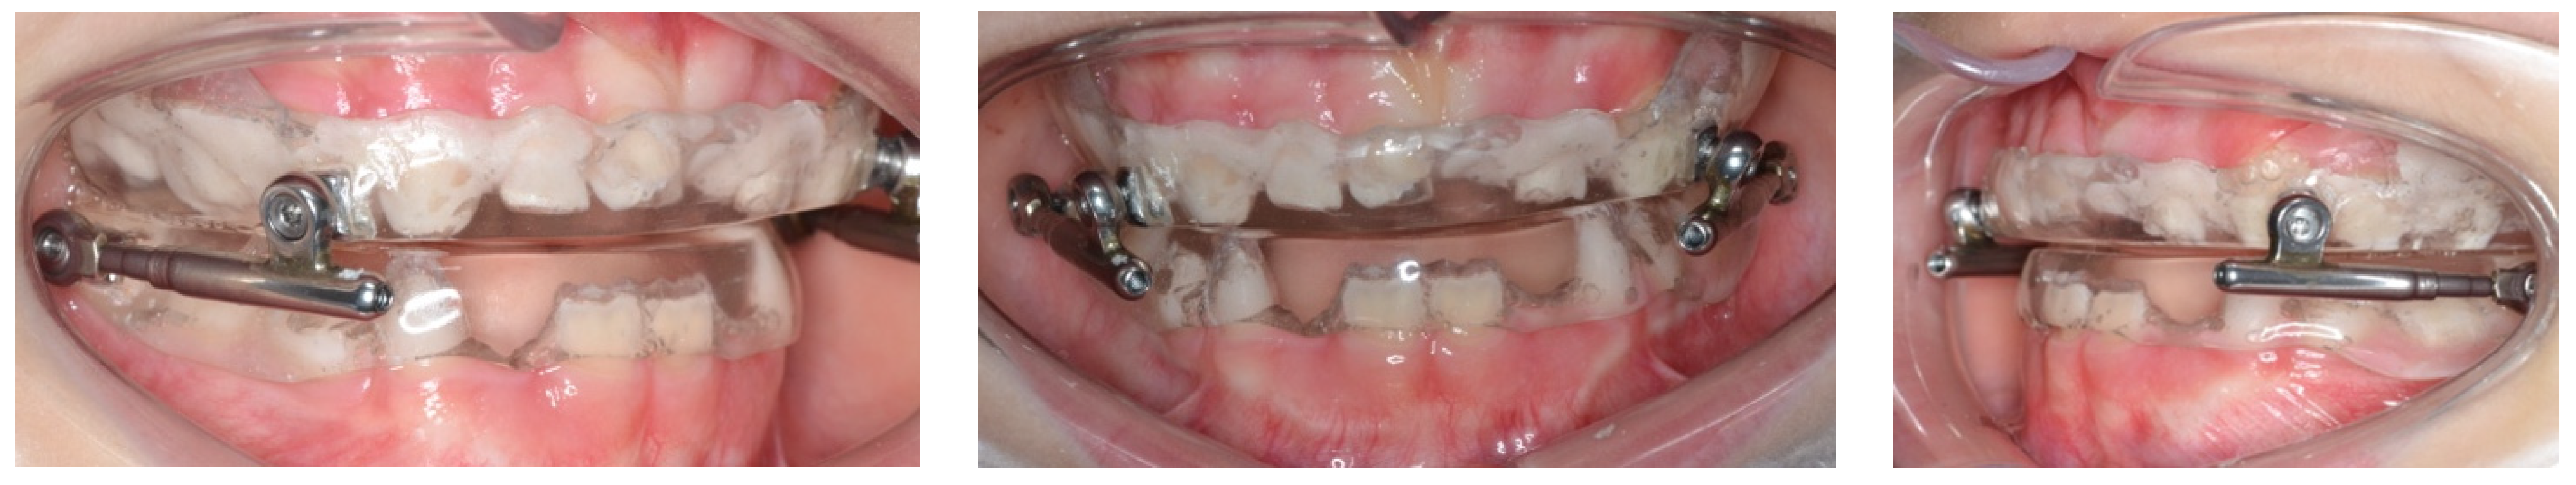

4. Treatment Progress